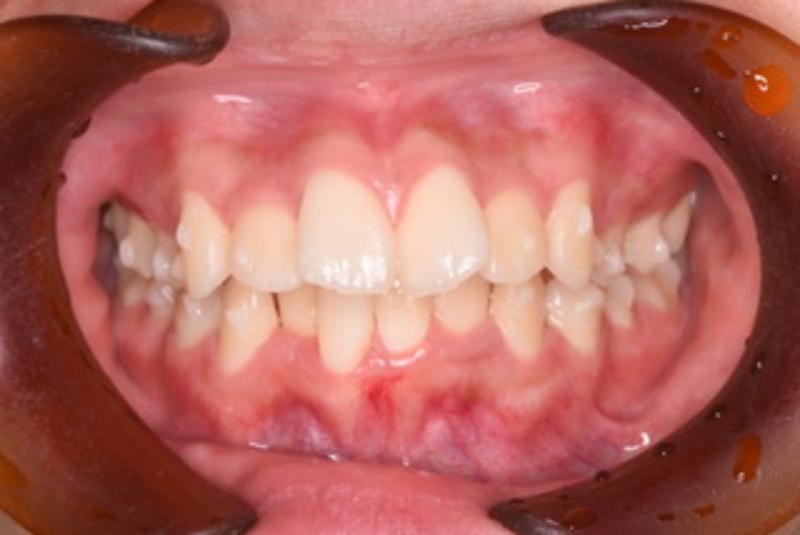

【術前】 【術中】 【術後】

前歯のガタつきと口元を引っ込めたい(口ゴボ)のため受診された16歳女性の方は、下顎前歯部のガタつきと、上顎の狭窄及び下顎の後退が予測されました。上顎の前歯をマウスピース矯正で引き込むだけでなく下顎を正常な位置まで戻すことで噛み合わせを再構築し、前歯のガタつきを抜歯する事なく改善できたそうです。

【治療部位】上顎・下顎

【治療期間】36ヶ月間

【治療回数】30回

【リスク】矯正しても横顔(口ゴボ)が改善しない事がある

【治療費用】精密検査:50,000円(税込)

一時矯正:900,000円(税込)

調整:0 円

合計:950,000円(税込)